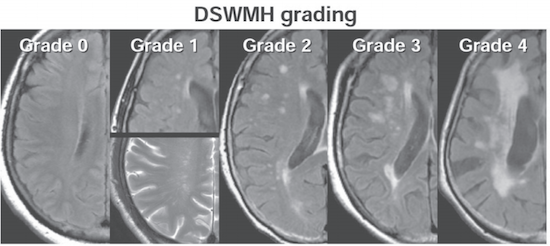

Fazekas grades. Fazekas степени мрт. Фазекас 2 мрт. Шкала Фазекас мрт. Лейкоареоз 3 степени по Fazekas.

Fazekas grades. Fazekas степени мрт. Фазекас 2 мрт. Шкала Фазекас мрт. Лейкоареоз 3 степени по Fazekas.

Fazekas grades. Классификация Фазекас. Fazekas мрт. Лейкоареоз степени по Fazekas. Фазекас классификация мрт.

Fazekas grades. Классификация Фазекас. Fazekas мрт. Лейкоареоз степени по Fazekas. Фазекас классификация мрт.

Fazekas grades. Фазекас классификация мрт. Лейкоареоз Fazekas 1 что это. Fazekas степени мрт. Лейкоареоз степени по Fazekas.

Fazekas grades. Фазекас классификация мрт. Лейкоареоз Fazekas 1 что это. Fazekas степени мрт. Лейкоареоз степени по Fazekas.

Fazekas grades. Фазекас 2. Fazekas 0. Фазекас 3.

Fazekas grades. Фазекас 2. Fazekas 0. Фазекас 3.